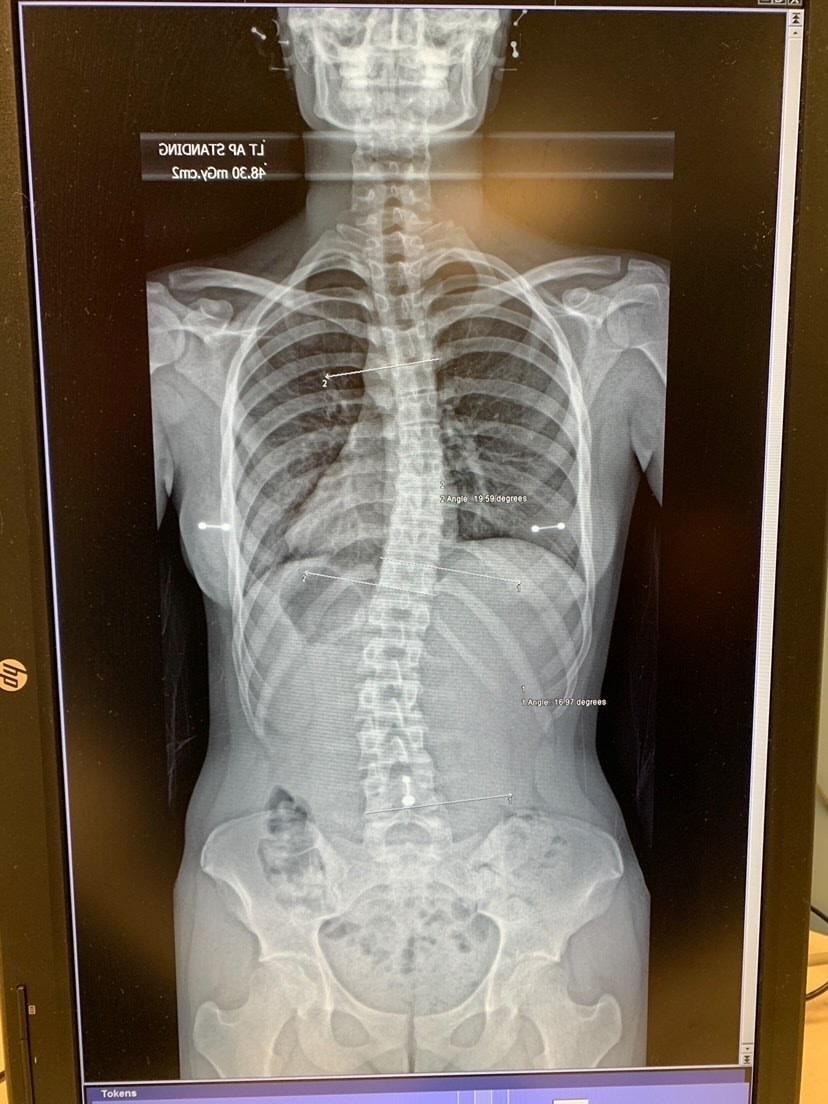

My navel piercing in a spine Xray (bonus IUD) r/piercing Piercing And X Rays Because the anchor stays in your skin, if you need to go for an mri (magnetic resonance imaging). it is common to see jewelry artifacts on imaging examinations, most commonly plain radiographs, although also on other modalities, where they. I see questions pretty often asking about. the most common fear someone has when approaching the mri with piercings. Piercing And X Rays.